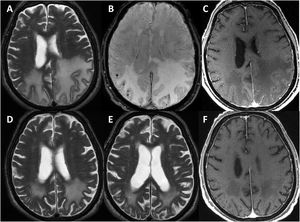

One patient was lost to follow-up. The remaining patients were followed up for a mean of 3.25 years (range, 0.5–6). All patients underwent at least one follow-up MRI study, 6 to 12 months after diagnosis (Fig. 3); 2 patients displayed radiological worsening after withdrawal of corticosteroids with a subsequent improvement after they were reintroduced. At the end of the follow-up period, 2 patients had died during the COVID-19 pandemic. According to the most recent reports from before they died, both patients presented moderate disability (mRS score of 3). Of the remaining 4 patients, 2 progressed favourably, with an acceptable level of independence (mRS < 3), and the other 2 presented torpid progression, with progressive cognitive decline and dependence in basic and instrumental activities of daily living (mRS > 3).

Radiological progression of patient 1 (an 81-year-old man).

Brain MRI revealed extensive bilateral parietal white matter involvement on T2-weighted sequences; involvement was asymmetrical, with a significant mass effect in the left hemisphere (A). White matter involvement coincided with multiple cortical microbleeds on susceptibility-weighted sequences (B) and predominantly left-sided leptomeningeal contrast uptake (C). Follow-up MRI studies performed at one month (D) and 3 months after corticosteroid treatment revealed a marked improvement of white matter involvement (E), with resolution of the mass effect and meningeal uptake (F).